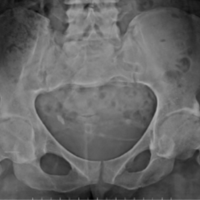

A 61-year-old unmarried male came with the complaints of right hip pain with the inability to bear weight on the right lower limb for 1 month. There was no history of trauma or other systemic symptoms. He had consulted the local practitioner, who advised an X-ray, which was reported as osteopoikilosis (spotted bone disease) by the radiologist. He was asked to take bed rest and analgesics but the pain persisted.

The patient then visited our tertiary center where the thorough skeletal survey was done, which showed involvement of pelvis (Fig. 1 and 2), spine (Fig. 3), and appendicular skeleton(Fig. 4 and 5) as well. The lesions were osteolytic, small, multiple, of varied sizes involving the whole of the involved bone, rather symmetrically (Fig. 6).